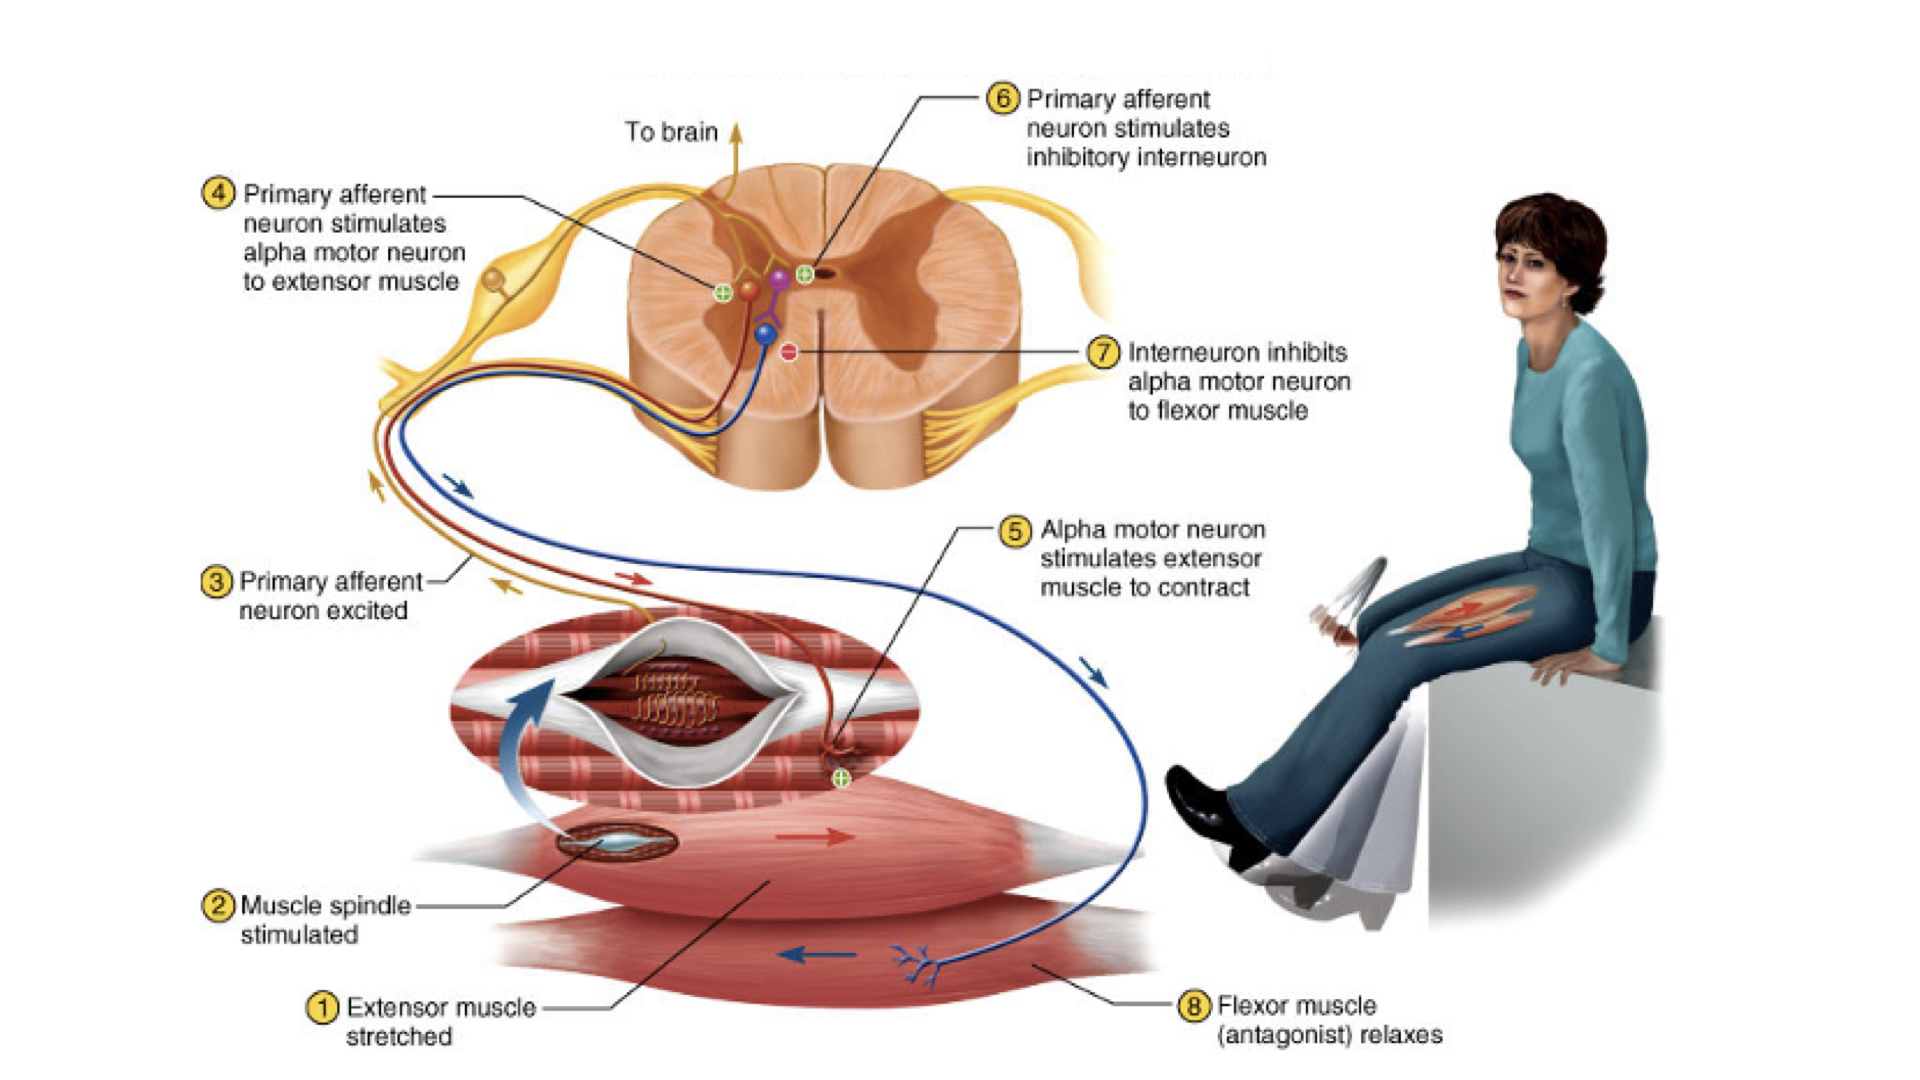

1. Monosynaptic - directly from sensory to motor neuron-- most rapid

2. Polysynaptic - from sensory to interneuron to motor neuron--slower and more complicated response

4. Patellar reflex

a. Reciprocal innervation